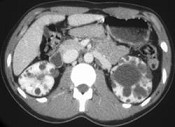

- 单项选择题男性,40岁, 因腰痛血尿就诊,B超检查发现肾脏增大, CT表现如图所示,追问病史发现家族中有类似疾病, 最可能考虑为 ( )

A、多囊肾

B、肾积水

C、多发性肾囊肿

D、肾肿瘤

E、肾结核